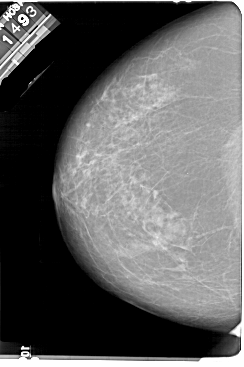

A_1858_1.LEFT_MLO

LEFT_MLO LINES 5491 PIXELS_PER_LINE 3826 BITS_PER_PIXEL 12 RESOLUTION 43.5 NON_OVERLAY